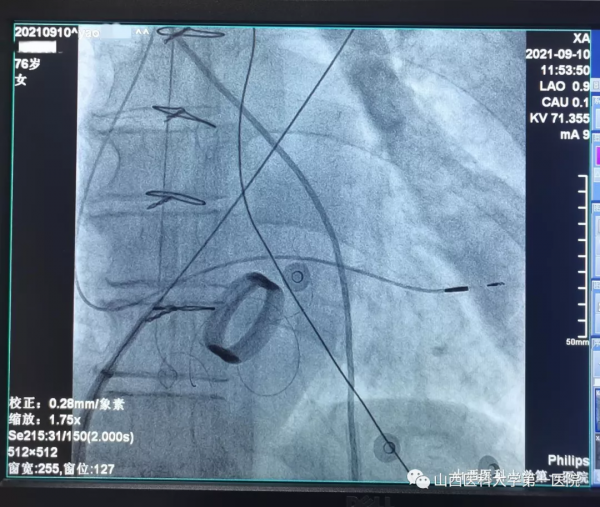

9月10日上午,心血管內科起搏電生理團隊王睿主任醫師、郭敏副主任醫師、張楠主治醫師經過近4小時的努力,順利完成手術。術中創新性地採用國際先進三維標測技術精準定位穿刺房間隔(T3D技術),並指引電極順利進入左室,簡化了手術流程,避免了以往報道中需穿刺動脈並藉助圈套器建立導絲軌道的操作,避免了對血管的損傷及相關併發症的發生。

王睿主任醫師介紹,三尖瓣機械瓣置換術後無法將心室起搏導線透過機械瓣進入右室,主要是由於起搏導線會影響機械瓣葉關閉,易導致三尖瓣嚴重反流,同時在此情況下極易損傷起搏導線,因而常規經靜脈右心室起搏被視為禁忌。但“上帝為你關了一扇門,總會為你開啟一扇窗”。電生理醫生的房間隔穿刺技術實現了經靜脈進入左心繫統的可能,為經靜脈左室心內膜起搏奠定了基礎。經房間隔左室心內膜起搏並非常規起搏術式,在全國乃至國際上的經驗較少,國內極少數中心有植入經驗,在既往報道中均體現了其手術難度大、操作複雜等特點,而目前該技術在山西省內仍處於空白。王睿主任醫師在術前仔細研究過往相關病例報道,反覆推敲手術過程,與團隊多次溝通手術細節,提前做好充分準備。術中聯合採用的T3D房間隔穿刺技術、三維指導下電極跨房間隔技術、無需圈套器鞘管進入左室、最細的雙極起搏導線植入等操作,在起搏器植入領域均屬於先進技術嘗試,術中多技術聯合應用為全球首例。